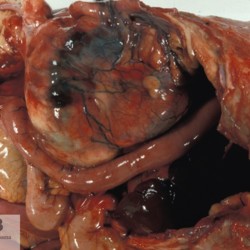

Etiquetes: N-173/96 de 2 Pàgina següent 6 total Canine Specie: Canine Organ: Kidney Lesion: Lymphoma Lesion modifier: - Disease: - Files/Expedient: N-173/96 Not viewed Canine Specie: Canine Organ: Kidney Lesion: Lymphoma Lesion modifier: - Disease: - Files/Expedient: N-173/96 Not viewed Canine Specie: Canine Organ: Kidney Lesion: Lymphoma Lesion modifier: - Disease: - Files/Expedient: N-173/96 Not viewed Canine Specie: Canine Organ: Kidney Lesion: Lymphoma Lesion modifier: - Disease: - Files/Expedient: N-173/96 Not viewed Canine Specie: Canine Organ: Heart Lesion: - Lesion modifier: - Disease: Dirofilariasis Files/Expedient: N-173/96 Not viewed de 2 Pàgina següent Títol Select...Avian (Exotic) (110)Avian (Poultry) (76)Bovine (317)Canine (935)Caprine (47)Equine (257)Feline (326)Ferret (19)General (127)Marine mammal (22)Non-human primate (20)Ovine (328)Porcine (379)Rabbit (61)Reptile (38)Rodent (28)Wildlife (91) Format Select...- (60)Abomasum (37)Adrenal gland (10)Blood (7)Blood vessel (50)Body as a whole (19)Bone (57)Bone marrow (21)Brain (93)Cloaca (1)Diaphragm (2)Ear (5)Esophagus (39)Eye (16)Fetus (12)Gallbladder (23)Gizzard (2)Heart (265)Intestine (356)Joint (32)Kidney (443)Larynx (5)Liver (326)Lung (264)Lymph node (91)Mammary gland (10)Mediastinum (1)Muscle (22)Nasal cavity (22)Nerve (7)Omasum (5)Oral cavity (63)Ovary (14)Oviduct (8)Pancreas (7)Parathyroid (5)Penis (10)Peritoneum (65)Pharynx (9)Pituitary gland (6)Placenta (7)Prostate (8)Proventriculus (3)Reticulum (1)Rumen (28)Sinus (7)Skin (181)Spinal cord (15)Spleen (105)Stomach (125)Teeth (1)Testicle (11)Thoracic cavity (31)Thymus (13)Thyroid gland (5)Tongue (32)Tonsils (11)Trachea (11)Urethra (5)Urinay bladder (61)Uterus (27)Vagina (1)Vulva (1)Yolk sac (1) Cobertura Select...- (152)Abomasitis (26)Abscess (27)Acidosis (1)Adenocarcinoma (20)Adenoma (9)Aerosacculitis (6)Agenesis (1)Agnathia (1)Alopecia (7)Amyloidosis (12)Aneurysm (6)Angiectasis (1)Anthracosis (1)Arteritis (11)Arthritis (15)Arthrogryposis (6)Artifact (4)Ascites (13)Atelectasis (8)Atherosclerosis (5)Atresia (1)Atrial septal defect (2)Atrophy (10)Autolysis (7)Bronchitis (6)Bronchopneumonia (26)Cachexia (2)Carcinoma (103)Cardiomyopathy (19)Cellulitis (2)Chemodectoma (4)Cholangiohepatitis (4)Cholangitis (19)Cholecystitis (4)Cholestasis (5)Chondrodysplasia (2)Chondrosarcoma (2)Chronic passive congestion (13)Chylothorax (2)Cirrhosis (6)Coelomitis (3)Coenurus cerebralis (4)Colitis (40)Congestion (17)Conjunctivitis (5)Coronitis (3)Cryptorchidism (3)Cyst (25)Cystitis (24)Dermatitis (69)Diaphragmatic hernia (4)Dilation (28)Discospondylitis (1)Disseminated intravascular coagulation (7)Dyschondroplasia (1)Dysplasia (29)Ectopia cordis (1)Ectopic ureter (1)Edema (55)Emphysema (5)Encephalitis (5)Endocardiosis (14)Endocarditis (26)Endometritis (5)Enteritis (118)Enterolith (6)Epulis (3)Esophagitis (14)Fasciitis (1)Fibrosis (7)Fibrous osteodystrophy (8)Fistula (1)Folliculitis (3)Fracture (2)Gastritis (34)Gingivitis (5)Glioma (8)Glomerulonephritis (21)Glossitis (25)Glycogenosis (1)Gout (8)Granuloma (2)Granulosa cell tumor (4)Hemangioma (9)Hemangiosarcoma (46)Hematoma (8)Hemoglobinuria (2)Hemopericardium (12)Hemoperitoneum (2)Hemorrhage (100)Hemosiderosis (7)Hemothorax (2)Hepatitis (78)Hernia (11)Histiocytosis (3)Hydatid cyst (11)Hydrocephalus (9)Hydrometra (1)Hydronephrosis (22)Hydropericardium (6)Hydrothorax (3)Hydroureter (5)Hyperkeratosis (8)Hyperostosis (4)Hyperplasia (37)Hypertrophy (9)Hypopigmentation (1)Hypoplasia (7)Hypopyon (1)Impaction (6)Infarction (63)Insulinoma (6)Intussusception (5)Jaundice (17)Laminitis (2)Laryngitis (2)Leiomyoma (5)Leukemia (13)Lipidosis (36)Lipoma (7)Lymphadenitis (45)Lymphadenopathy (7)Lymphangiectasia (6)Lymphangitis (5)Lymphoma (221)Malacia (11)Malignant melanoma (15)Mast cell tumor (11)Mastitis (8)Megaesophagus (2)Melanosis (3)Melena (4)Meningioma (6)Meningitis (6)Meningocele (2)Meningoencephalitis (5)Mesothelioma (5)Methemoglobinemia (2)Mineralization (10)Mucocele (5)Mucometra (1)Multilobular bone tumor (1)Mummification (3)Myelofibrosis (1)Myocarditis (4)Myositis (5)Necrosis (81)Nephritis (113)Nephroblastoma (6)Nephrosclerosis (1)Nephrosis (14)Neuritis (1)Obstruction (13)Omasitis (4)Omphalitis (1)Omphalophlebitis (7)Orchitis (4)Osteoarthrosis (5)Osteomyelitis (9)Otitis (2)Palatoschisis (3)Pancreatitis (3)Panniculitis (3)Papilloma (7)Parakeratosis (14)Patent ductus arteriosus (6)Peliosis hepatis (1)Perforation (17)Pericarditis (35)Peritonitis (39)Persistent right aortic arch (1)Pharyngitis (2)Pheochromocytoma (2)Phlebitis (2)Placentitis (6)Pleuritis (21)Pleuropneumonia (24)Pneumonia (109)Pneumothorax (3)Polycystosis (14)Polyp (5)Polyserositis (6)Posthitis (1)Proctitis (4)Prolapse (3)Prostatitis (3)Proventriculitis (1)Pyelonephritis (24)Pyometra (6)Pyothorax (4)Rhinitis (11)Rumenitis (6)Rupture (24)Salpingitis (3)Sarcoma (57)Sclerosis (1)Scoliosis (2)Seminoma (2)Sequestrum (2)Serous atrophy (14)Sinusitis (7)Splenitis (14)Splenomegaly (9)Spondylitis (6)Spondylosis (1)Stenosis (9)Stomatitis (32)Tenosynovitis (2)Teratoma (3)Thricobezoar (2)Thrombosis (16)Tonsilitis (4)Torsion (13)Tracheitis (4)Tympany (7)Typhlitis (8)Typhlocolitis (4)Ulcer (43)Urethritis (1)Urolithiasis (36)Uroperitoneum (1)Uveitis (1)Vasculitis (15)Ventricular septal defect (3)Volvulus (11) Matèria Select... - (14)- (1653)- (152)Abomasitis - Catarrhal (2)Abomasitis - Catarrhal-hemorrhagic (1)Abomasitis - Chronic (1)Abomasitis - Fibrinous-necrotizing (2)Abomasitis - Hyperplasic (5)Abomasitis - Hyperplasic - Chronic (1)Abomasitis - Necrotic (1)Abomasitis - Necrotizing (2)Abomasitis - Ulcerative (5)Adenocarcinoma (9)Aerosacculitis - Granulomatous (1)Amyloidosis - Chronic (1)Arteritis - Necrotic (2)Arteritis - Necrotizing (1)Arthritis - Chronic (4)Arthritis - Fibrinous-purulent (3)Arthritis - Serous (4)Arthritis - Subacute (1)Ascites - Serous (1)Atrophy - Serous (1)Bronchitis - Catarrhal (3)Bronchitis - Suppurative (1)Bronchopneumonia - Catarrhal-purulent (17)Bronchopneumonia - Fibrinous (1)Bronchopneumonia - Granulomatous (1)Bronchopneumonia - Purulent (1)Bronchopneumonia - Suppurative (5)Carcinoma - Adenocarcinoma (33)Carcinoma - Adenocarcinoma - Hepatocellular (2)Carcinoma - Adenocarcinoma - Mucinous (1)Carcinoma - Basosquamous (1)Carcinoma - Cholangiocellular (3)Carcinoma - Hepatocellular (4)Carcinoma - Metastatic (3)Carcinoma - Squamous cell carcinoma (13)Carcinoma - Transitional cell (2)Cardiomyopathy - Dilated (13)Cardiomyopathy - Hypertrophic (6)Cellulitis - Necrotizing (1)Cholangitis - Chronic (8)Cholangitis - Hyperplasic (3)Cholecystitis - Fibrinous-necrotizing (1)Coelomitis - Fibrinous (1)Coelomitis - Granulomatous (1)Colitis - Catarrhal (3)Colitis - Catarrhal-hemorrhagic (1)Colitis - Fibrinous (1)Colitis - Fibrinous-necrotizing (1)Colitis - Fibrinous-necrotizing (Diphtheritic) (6)Colitis - Granulomatous (2)Colitis - Hemorrhagic (4)Colitis - Hemorrhagic-necrotizing (3)Colitis - Necrotizing (2)Colitis - Ulcerative (6)Congestion - Chronic (2)Conjunctivitis - Hyperplasic (1)Conjunctivitis - Purulent (3)Coronitis - Ulcerative (1)Cystitis - Chronic (3)Cystitis - Fibrinous (1)Cystitis - Fibrinous-necrotizing (1)Cystitis - Follicular (1)Cystitis - Hemorrhagic (6)Cystitis - Hemorrhagic-ulcerative (1)Cystitis - Necrotizing (9)Cystitis - Perforated (1)Dermatitis - Granulomatous (14)Dermatitis - Hyperkeratotic (10)Dermatitis - Hyperplasic (proliferative) (1)Dermatitis - Hyperplastic (10)Dermatitis - Necrotizing (4)Dermatitis - Pustular (4)Dermatitis - Ulcerative (2)Dilation - Chronic (1)Discospondylitis - Necrotizing (1)Dysplasia - Follicular (5)Edema - Interstitial (6)Emphysema - Interstitial (1)Encephalitis - Granulomatous (1)Encephalitis - Nonsuppurative (1)Endocardiosis - Mitral (7)Endocardiosis - Mitral - Chronic (5)Endocarditis - Valvular (6)Endocarditis - Valvular - Mitral (7)Endocarditis - Valvular - Pulmonic (1)Endocarditis - Valvular - Subacute (1)Endocarditis - Valvular - Subaortic (5)Endocarditis - Valvular - Tricuspid (4)Endometritis - Purulent (3)Endometritis - Purulent-hemorrhagic (2)Enteritis - Catarrhal (23)Enteritis - Catarrhal - Acute (1)Enteritis - Catarrhal-hemorrhagic (5)Enteritis - Catarrhal-hemorrhagic - Acute (2)Enteritis - Fibrinous (16)Enteritis - Fibrinous - Acute (3)Enteritis - Fibrinous-necrotizing (7)Enteritis - Granulomatous (14)Enteritis - Granulomatous - Chronic (1)Enteritis - Granulomatous - Multifocal (1)Enteritis - Hemorrhagic (17)Enteritis - Hemorrhagic - Acute (1)Enteritis - Hemorrhagic-necrotizing (1)Enteritis - Hyperplasic (proliferative) (4)Enteritis - Necrotizing (4)Enteritis - Necrotizing - Acute (1)Enteritis - Necrotizing - Hemorrhagic (1)Enteritis - Necrotizing-ulcerative (2)Enteritis - Ulcerative (1)Enteritis - Ulcerative-hemorrhagic (1)Esophagitis - Erosive-ulcerative (6)Esophagitis - Necrotizing (4)Esophagitis - Ulcerative (1)Esophagitis - Ulcerative-necrotizing (1)Fasciitis - Fibrinous-purulent (1)Folliculitis - Purulent (2)Gastritis - Catarrhal (2)Gastritis - Chronic (1)Gastritis - Follicular (1)Gastritis - Hemorrhagic (2)Gastritis - Hemorrhagic-necrotizing (1)Gastritis - Hypertrophic (2)Gastritis - Inclusion bodies (1)Gastritis - Mineralization (1)Gastritis - Mycotic (1)Gastritis - Necrotizing (2)Gastritis - Ulcerative (6)Gastritis - Uremic (3)Gingivitis - Erosive (2)Gingivitis - Hyperplasic (proliferative) (1)Gingivitis - Necrotizing (1)Glomerulonephritis - Chronic (7)Glomerulonephritis - Membranoproliferative (3)Glomerulonephritis - Membranoproliferative - Chronic (1)Glomerulonephritis - Membranous (3)Glomerulonephritis - Membranous - Chronic (1)Glomerulonephritis - Proliferative (2)Glomerulonephritis - Subacute (1)Glossitis - Erosive (2)Glossitis - Granulomatous (6)Glossitis - Hyperplasic (1)Glossitis - Hyperplasic (proliferative) (2)Glossitis - Hyperplastic (1)Glossitis - Necrotizing (2)Glossitis - Necrotizing - Focal (1)Glossitis - Ulcerative (6)Glossitis - Ulcerative - Multifocal (1)Glossitis - Ulcerative - Subacute (1)Glycogenosis (1)Granuloma - Eosinophilic (1)Hemangiosarcoma - Metastatic (2)Hemorrhage - Acute (1)Hemorrhage - Subcapsular (3)Hepatitis - Abscess (9)Hepatitis - Acute (3)Hepatitis - Chronic (4)Hepatitis - Chronic interstitial (6)Hepatitis - Granulomatous (7)Hepatitis - Interstitial - Multifocal (1)Hepatitis - Interstitial - Subacute (1)Hepatitis - Necrotizing (17)Hepatitis - Necrotizing - Acute (2)Hepatitis - Necrotizing - Hemorrhagic (1)Hepatitis - Necrotizing - Subacute (1)Hepatitis - Pyogranulomatous (7)Hepatitis - Subacute (4)Hydronephrosis - Chronic (1)Hydropericardium - Chronic (1)Hyperplasia - Erythroid (1)Hyperplasia - Lymphoid (3)Hyperplasia - Myeloid (1)Hyperplasia - Nodular (8)Hypertrophy - Concentric (2)Hypertrophy - Eccentric (3)Infarction - Acute (17)Infarction - Acute - Multifocal (2)Infarction - Chronic (5)Infarction - Chronic - Multifocal (1)Infarction - Subacute (18)Infarction - Subacute - Focal (2)Laminitis - Chronic (2)Laryngitis - Necrotic (1)Laryngitis - Necrotizing (1)Leukemia - Lymphoid leukemia (2)Leukemia - Non-lymphoid leukemia (6)Lipidosis - Multifocal (1)Lipidosis - Panlobular (1)Lipidosis - Panlobular - Generalized (2)Lymphadenitis - Granulomatous (24)Lymphadenitis - Granulomatous - Chronic (3)Lymphadenitis - Hemorrhagic (1)Lymphadenitis - Necrotizing (5)Lymphadenitis - Necrotizing (caseous) (11)Lymphangitis - Granulomatous (1)Lymphangitis - Purulent (1)Lymphangitis - Ulcerative (1)Lymphoma - Alimentary lymphoma (7)Lymphoma - Cutaneous lymphoma (6)Lymphoma - Lymphosarcoma (2)Lymphoma - Mediastinal lymphoma (1)Lymphoma - Multicentric lymphoma (29)Malignant melanoma - Malignant (1)Malignant melanoma - Metastatic (1)Mast cell tumor - Metastatic (1)Mastitis - Fibrinous-purulent (2)Mastitis - Necrotic (1)Mastitis - Purulent (3)Mastitis - Suppurative (1)Meningitis - Fibrinous-purulent (2)Meningitis - Purulent (4)Meningoencephalitis - Necrotizing (3)Meningoencephalitis - Nonsuppurative (2)Mineralization - Metastatic (4)Myocarditis - Fibrous - Chronic (1)Myocarditis - Granulomatous (1)Myositis - Purulent (2)Necrosis - Acute (1)Necrosis - Cortical (5)Necrosis - Follicular (1)Necrosis - Papillary (8)Necrosis - Papillary - Acute (3)Necrosis - Subacute (3)Necrosis - Tubular (6)Nephritis - Embolic (2)Nephritis - Embolic suppurative (7)Nephritis - Granulomatous (27)Nephritis - Granulomatous - Chronic (1)Nephritis - Granulomatous - Multifocal (1)Nephritis - Interstitial (6)Nephritis - Interstitial - Acute (4)Nephritis - Interstitial - Chronic (41)Nephritis - Interstitial - Subacute (12)Nephritis - Purulent (7)Nephritis - Purulent - Acute (2)Nephritis - Purulent - Multifocal (3)Nephrosis - Cholemic (3)Nephrosis - Hemoglobinuric (10)Omasitis - Fibrinous-necrotizing (1)Omasitis - Hyperkeratotic (1)Omasitis - Necrotizing (2)Omphalophlebitis - Fibrinous-purulent (2)Omphalophlebitis - Purulent (3)Orchitis - Necrotizing (1)Osteomyelitis - Necrotizing (7)Osteomyelitis - Purulent (2)Otitis - Necrotizing (1)Otitis - Proliferative (1)Pancreatitis - Acute (1)Pancreatitis - Chronic (1)Pancreatitis - Granulomatous (1)Panniculitis - Fibrinous-purulent (1)Panniculitis - Necrotic (1)Panniculitis - Parasitic (1)Perforation - Acute (2)Pericarditis - Fibrinous (19)Pericarditis - Fibrinous - Subacute (1)Pericarditis - Fibrinous-necrotizing (1)Pericarditis - Fibrinous-purulent (3)Pericarditis - Fibrous (1)Pericarditis - Fibrous - Chronic (1)Pericarditis - Gangrenous (6)Pericarditis - Granulomatous (1)Pericarditis - Granulomatous - Chronic (2)Peritonitis - Acute (1)Peritonitis - Fibrinous (11)Peritonitis - Fibrinous - Subacute (1)Peritonitis - Fibrinous-purulent (5)Peritonitis - Fibrous (3)Peritonitis - Granulomatous (6)Peritonitis - Purulent (1)Peritonitis - Purulent-hemorrhagic (1)Peritonitis - Pyogranulomatous (3)Pharyngitis - Fibrinous-necrotizing (1)Pharyngitis - Ulcerative (1)Pheochromocytoma - Metastatic (1)Phlebitis - Purulent (1)Placentitis - Fibrinous-necrotizing (1)Placentitis - Necrotic (1)Placentitis - Necrotizing (1)Pleuritis - Chronic (1)Pleuritis - Fibrinous (3)Pleuritis - Fibrinous-purulent (2)Pleuritis - Fibrous (2)Pleuritis - Granulomatous (3)Pleuritis - Hyperplastic (2)Pleuritis - Purulent (2)Pleuritis - Pyogranulomatous (1)Pleuropneumonia - Fibrinous (13)Pleuropneumonia - Fibrinous-necrotizing (5)Pleuropneumonia - Granulomatous (2)Pleuropneumonia - Hemorrhagic-necrotizing (4)Pneumonia - Aspiration (11)Pneumonia - Bronchointerstitial (4)Pneumonia - Bronchointerstitial - Subacute (1)Pneumonia - Embolic (5)Pneumonia - Granulomatous (37)Pneumonia - Granulomatous - Multifocal (4)Pneumonia - Hemorrhagic-necrotizing (2)Pneumonia - Interstitial (7)Pneumonia - Interstitial - Acute (8)Pneumonia - Interstitial - Chronic (6)Pneumonia - Interstitial - Subacute (15)Pneumonia - Necrotizing (2)Pneumonia - Pyogranulomatous (2)Pneumonia - Verminous (5)Polyserositis - Fibrinous (6)Polyserositis - Fibrous (1)Proctitis - Fibrinous-necrotizing (1)Proctitis - Parasitic (2)Prostatitis - Purulent (1)Pyelonephritis - Acute (2)Pyelonephritis - Chronic (3)Rhinitis - Catarrhal (2)Rhinitis - Fibrinous (1)Rhinitis - Granulomatous (4)Rhinitis - Purulent (3)Rumenitis - Acute (1)Rumenitis - Erosive (1)Rumenitis - Necrotizing (1)Rupture - Acute (3)Sarcoma - Fibrosarcoma (12)Sarcoma - Hemangiosarcoma (11)Sarcoma - Histiocytic (7)Sarcoma - Metastatic (1)Sarcoma - Multilobular tumor of bone (1)Sequestrum - Chronic (2)Sinusitis - Suppurative (1)Splenitis - Granulomatous (8)Splenitis - Granulomatous - Chronic (1)Splenitis - Necrotizing (3)Splenitis - Necrotizing (caseous) (2)Spondylitis - Necrotizing (2)Stenosis - Intestinal (1)Stenosis - Valvular - Subaortic (4)Stomatitis - Erosive (12)Stomatitis - Erosive-ulcerative (3)Stomatitis - Fibrinous-necrotizing (1)Stomatitis - Fibrinous-necrotizing (Diphtheritic) (1)Stomatitis - Granulomatous (1)Stomatitis - Hyperplasic (1)Stomatitis - Hyperplasic (proliferative) (1)Stomatitis - Necrotizing (2)Stomatitis - Ulcerative (5)Stomatitis - Ulcerative - Multifocal (1)Stomatitis - Ulcerative-necrotizing (1)Tonsilitis - Necrotizing (4)Torsion - Acute passive hyperemia (5)Tracheitis - Catarrhal (3)Tracheitis - Fibrinous (1)Tracheitis - Granulomatous (1)Typhlitis - Catarrhal (1)Typhlitis - Fibrinous-necrotizing (2)Typhlitis - Hemorrhagic (2)Typhlitis - Ulcerative-hemorrhagic (1)Typhlocolitis - Fibrinous-necrotizing (2)Typhlocolitis - Proliferative (1)Ulcer - Chronic (6)Ulcer - Multifocal (2)Ulcer - Mycotic (1)Ulcer - Perforated (6)Urethritis - Hemorrhagic (1)Urolithiasis - Chronic (2)Uveitis - Granulomatous (1)Vasculitis - Granulomatous (1)Vasculitis - Necrotizing (1) Editor Select...- (1970)Acidosis (2)Actinobacillosis (Pleuropneumonia) (11)Aelurostrongylosis (2)African horse sickness (13)African swine fever (14)Alopecia X (1)Anaplasmosis (4)Anthrax (2)Aortic thromboembolism (feline) (7)Ascariasis (15)Aspergillosis (18)Atopic dermatitis (1)Atrophic rhinitis (3)Babesiosis (6)Blackhead (1)Bluetongue (11)Border disease (2)Bovine viral diarrhea (21)Brucellosis (2)Candidiasis (5)Canine distemper (14)Caprine arthritis-encephalitis (2)Capture myopathy (1)Cardiac insufficiency (17)Caseous lymphadenitis (7)Chlamydiosis (2)Classical swine fever (19)Clostridiosis (19)Coccidiosis (9)Coenurosis (4)Colibacillosis (21)Contagious ecthyma (7)Copper toxicosis (11)Cowdriosis (Heartwater) (3)Cryptococcosis (3)Cryptosporidiosis (2)Cysticercosis (23)Demodicosis (1)Diabetes (1)Dicrocoeliosis (5)Dictyocaulosis (4)Dirofilariasis (7)Discoid lupus erythematosus (3)Echinococcosis (17)Edema disease (7)Egg drop syndrome (1)Encephalitozoonosis (5)Enterotoxemia (1)Enzootic bovine leukosis (46)Epitheliogenesis imperfecta (3)Equine rhinopneumonitis (2)Equine verminous arteritis (strongylosis) (7)Erysipelas (5)Exudative epidermitis (7)Fasciolasis (11)Feline eosinophilic dermatoses (1)Feline hepatic lipidosis (8)Feline histiocytosis (4)Feline infectious peritonitis (38)Feline leukemia (4)Feline lower urinary tract disease (3)Feline panleukopenia (16)Feline viral rhinotracheitis (1)Flea allergy dermatitis (1)Foot and mouth disease (2)Gasterophilosis (4)Glasser's disease (15)Gousiekte (4)Gout (6)Haemonchosis (9)Hemolytic anemia (4)Hemorrhagic diathesis (1)Hepatic insufficiency (11)Hepatosis dietetica (7)Herpesvirosis (6)Hyperadrenocorticism (7)Hyperparathyroidism (10)Hypertrophic osteopathy (6)Hypervitaminosis D (1)Hypodermosis (1)Inclusion body hepatitis (4)Infectious bovine rhinotracheitis (5)Infectious bronchitis (5)Infectious canine hepatitis (13)Influenza (4)Juvenile nephropathy (8)Lamb dysentery (4)Leishmaniasis (28)Leptospirosis (1)Leukosis (5)Listeriosis (4)Lumpy skin disease (3)Maedi-visna (4)Malignant catarrhal fever (12)Mange (6)Mannheimiosis (5)Marek's disease (7)Metabolic bone disease (2)Mucoid enteropathy (5)Mulberry heart disease (5)Myasis (1)Mycobacteriosis (22)Mycosis fungoides (6)Myxomatosis (3)Necrobacillosis (5)Neonatal isoerythrolysis (6)Nocardiosis (4)Oestrosis (2)Onchocerciasis (1)Osteochondrosis (1)Ostertagiosis (6)Ovine pulmonary adenocarcinoma (5)Oxyuriasis (1)Pacheco's disease (4)Papillomatosis (6)Paratuberculosis (18)Parvovirosis (17)Pasteurellosis (11)Pemphigus foliaceus (1)Periodontal disease (1)Polioencephalomalacia of ruminants (4)Polyarteritis nodosa (3)Polycystic kidney disease (13)Porcine circovirosis (11)Porcine dermatitis and nephropathy syndrome (9)Porcine proliferative enteropathy (4)Porcine reproductive and respiratory syndrome (6)Porcine stress syndrome (1)Pox (13)Pregnancy toxemia (3)Proventricular dilatation disease (2)Pseudotuberculosis (yersiniosis) (2)Psittacine beak and feather disease (PBFD) (5)Pyoderma (4)Q fever (4)Rabbit hemorrhagic disease (2)Renal insufficiency (12)Reticuloendotheliosis (2)Rhodococcosis (1)Rickets (1)Rinderpest (2)Salmonellosis (34)Sarcosporidiosis (2)Schmallenberg (7)Septicemia (23)Spirocercosis (11)Streptococcosis (5)Strongylosis (1)Swine dysentery (5)Systemic coronavirosis (5)Tetralogy of Fallot (5)Theileriosis (13)Thromboembolism (5)Toxoplasmosis (11)Transmissible viral proventriculitis (1)Traumatic reticuloperitonitis (3)Traumatism (16)Tuberculosis (58)Ulcerative lymphangitis (1)Uremic syndrome (20)Viral arthritis (6)White muscle disease (9)Wobbler syndrome (2)Xanthomatosis (1)Zygomycosis (4) Idioma Select...- (1180)Bacterial (501)Degeneration (106)Fungal (46)Hemodynamic (112)Idiopathic (22)Inflammation (58)Malformation (88)Neoplasia (343)Nutritional (41)Parasitic (243)Physical/Chemical (93)Toxic (44)Viral (304) Ítem destacat Bovine Anaplasma marginale (extravascular haemolytic anemia). Blood smear abtained postmortem from cut ear capillaries.University of Pretoria, South Africa